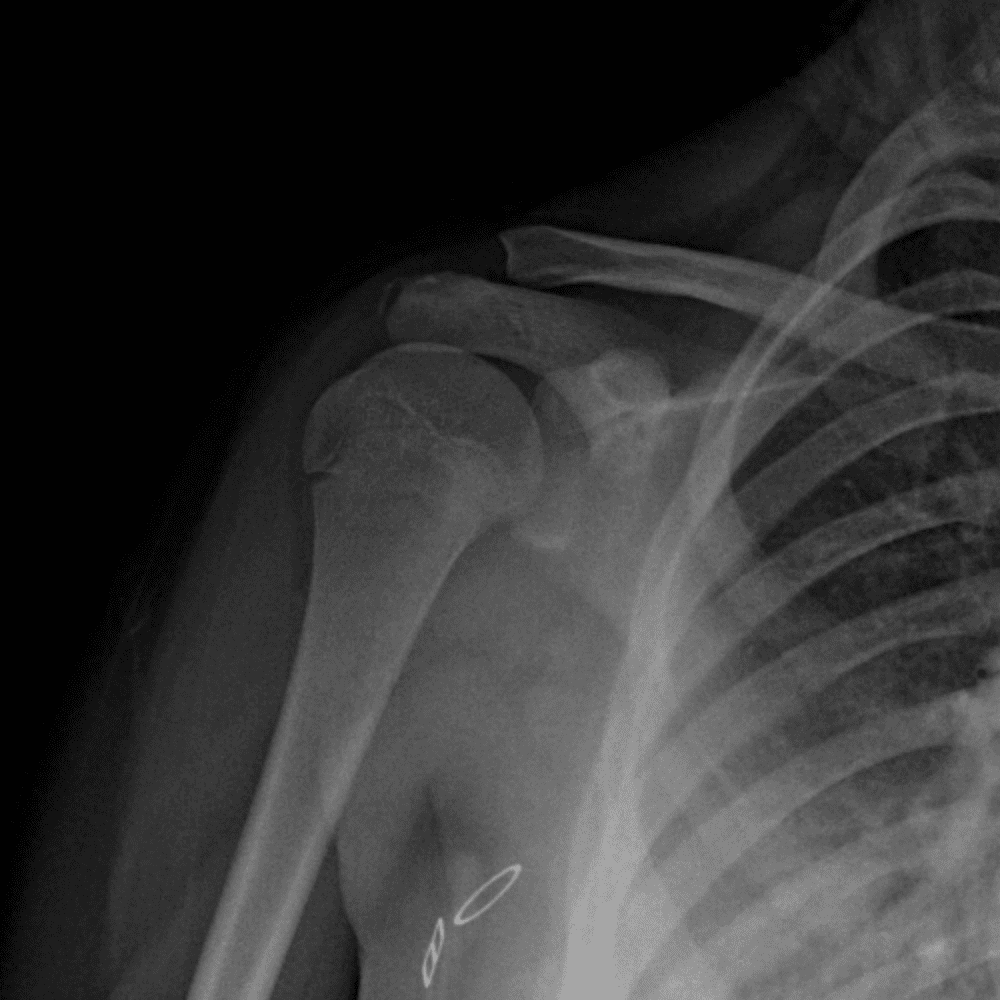

Simuliert den Dienst durch subtile oder schwierige Fälle und einige Normalbefunde.

30 Fälle